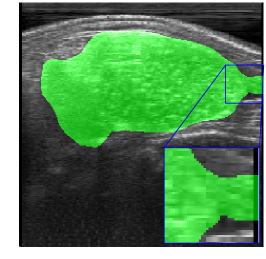

Figs. 2 and 3 present examples that illustrate the challenges of semantic segmentation methods. The trees in Fig. 2 show that in most images the foreground covers fewer pixels than the background (class imbalance). Besides, trees have edges that are difficult to label, and some pixels may be incorrectly labeled. Fig. 3 also illustrates the labeling challenge, in which some parts of the object are not visible in the image due to noise when capturing images.

Rib Eye Area (REA). This image dataset consists of ultrasound images of the Longissimus dorsi muscle between the 11th and 13th ribs of cattle. The goal is to automatically calculate the rib eye area (REA), an important region for decision making during cattle breeding. The main challenge is the uncertainty in the REA annotation, since the image is noisy and even experts have difficulty in delimiting the borders of this region. Fig. 3 presents examples of images and the annotation made by a specialist. We can observe that some borders are absent and depend on the subjectivity and knowledge of the annotator. To evaluate the segmentation methods, 76 images with resolution were obtained and labeled by an expert. Due to the number of images, the division of the images in training and testing followed 5-fold cross-validation.

REA dataset. This image dataset has high uncertainty during labeling due to noise from the ultrasound image. In some cases, the border of REA is not completely visible and must be estimated by the specialist. Therefore, the proposed approach becomes essential to obtain accurate segmentation at the edges. The segmentation examples in Fig. 6 show that the baseline was not able to define the REA correctly due to the uncertainty of the labeling. On the other hand, the proposed approach presents results close to the specialist in regions that the border needs to be estimated.